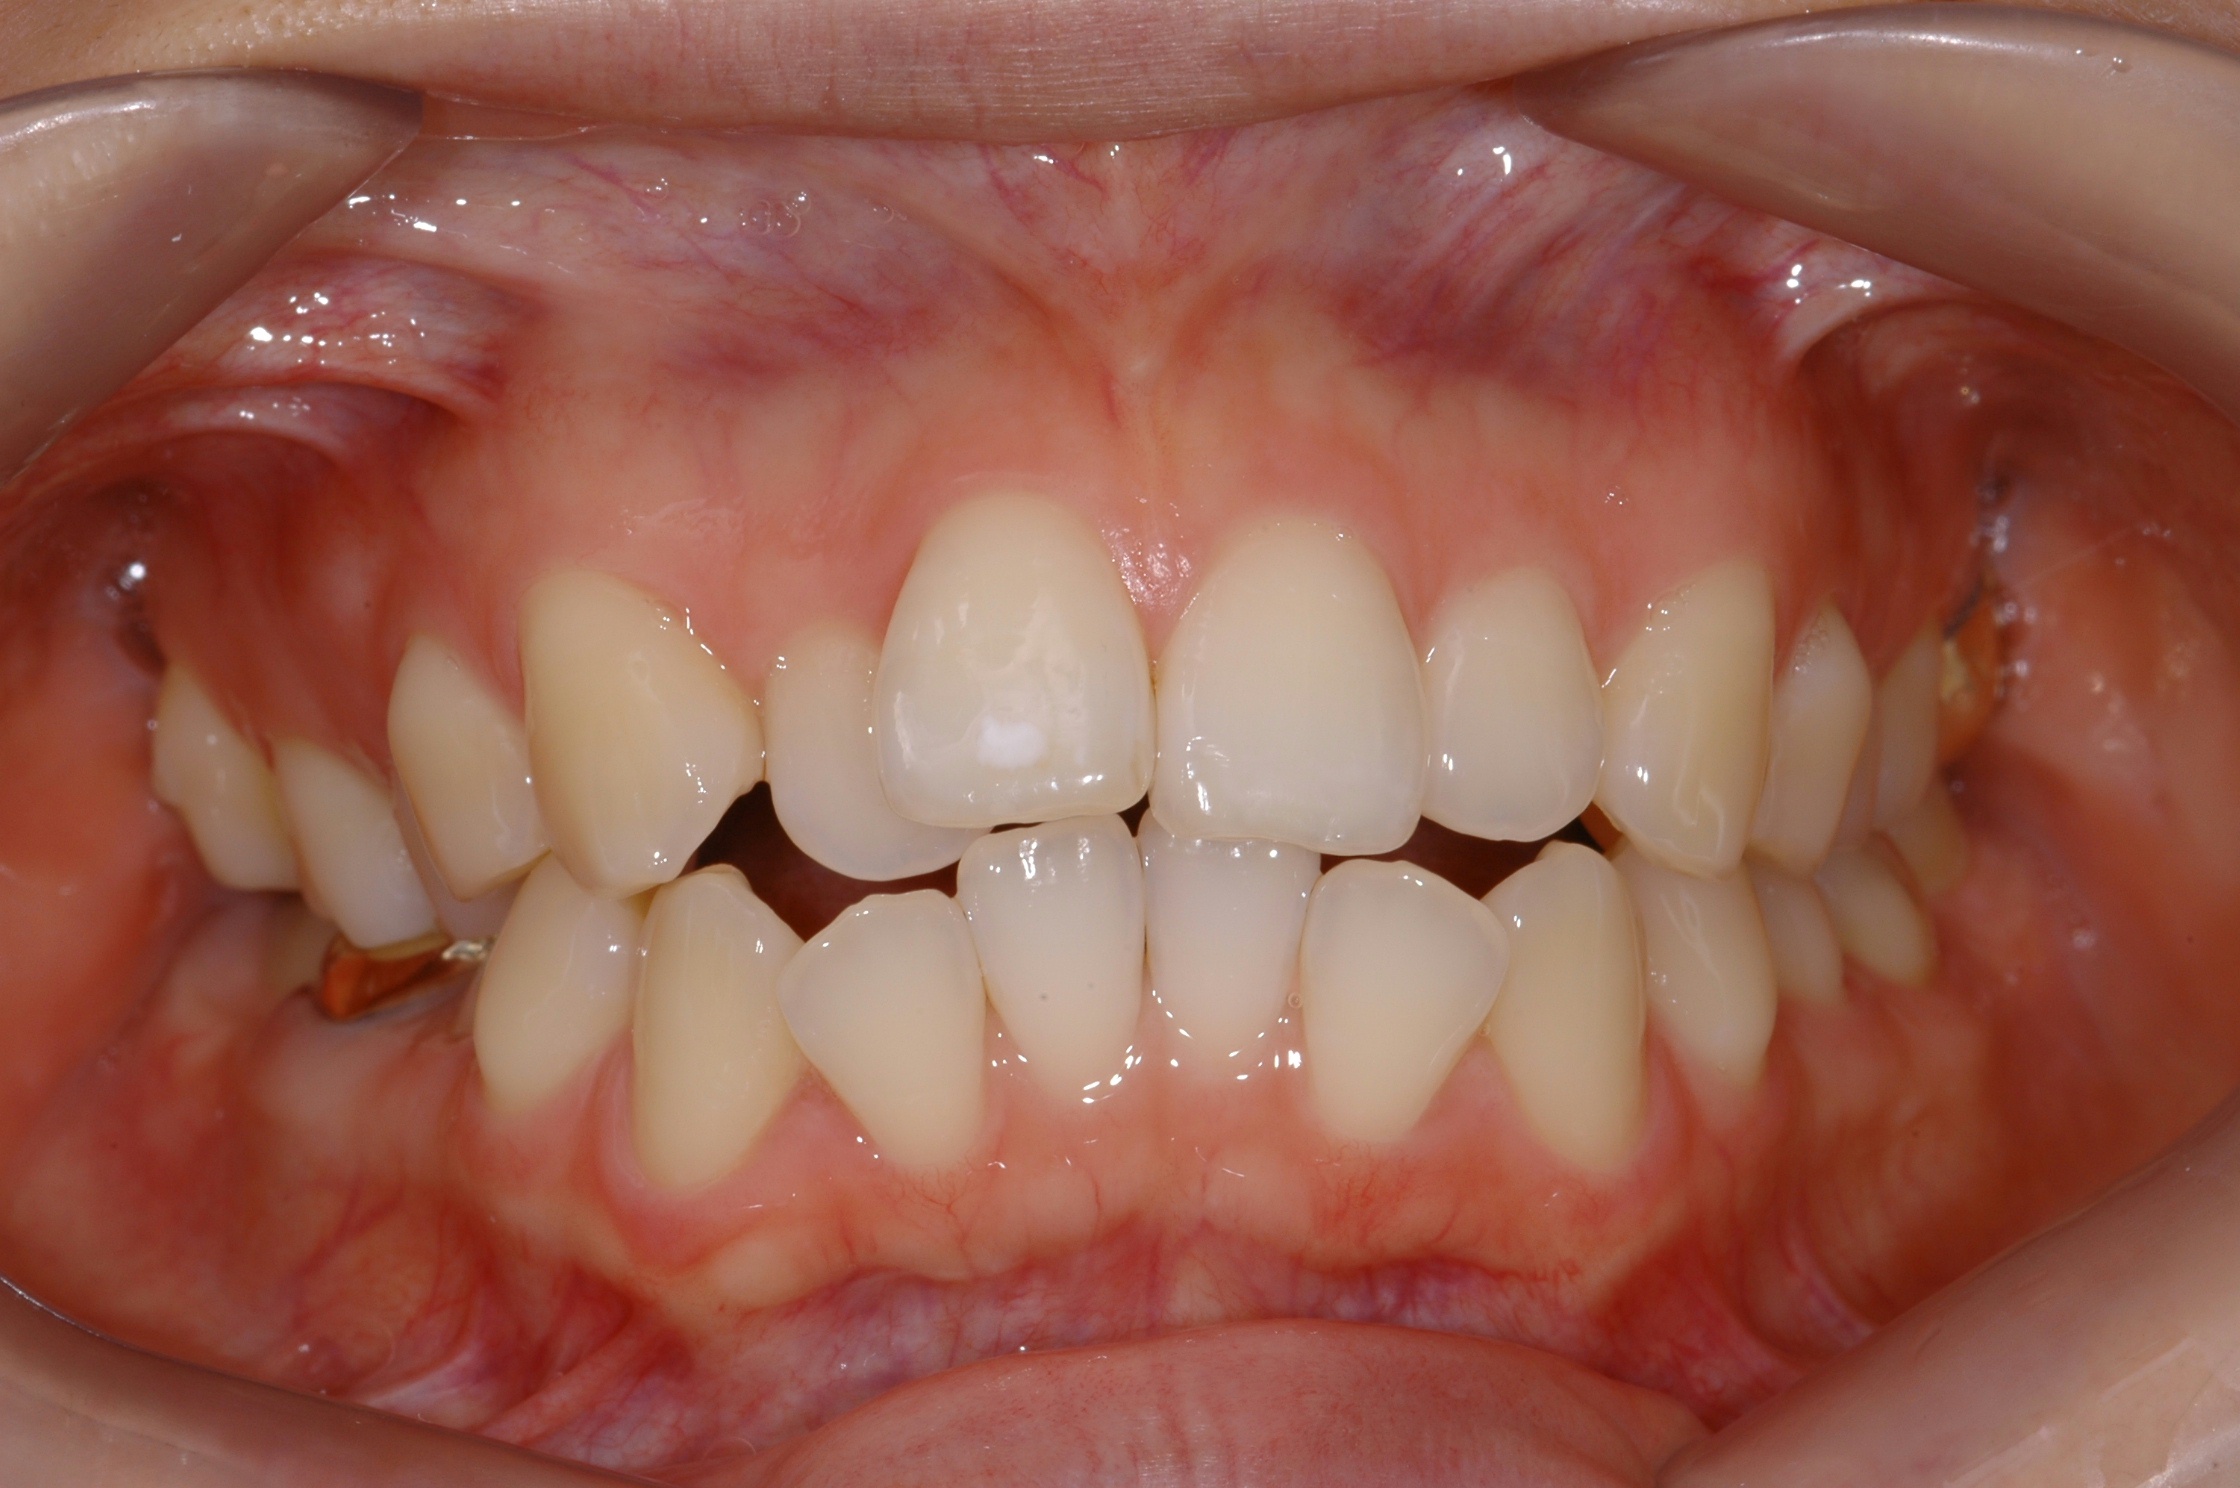

치료 전 사진입니다.